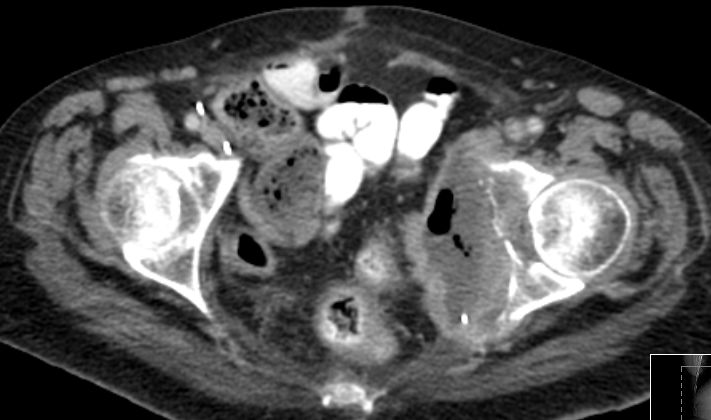

| Becken-Rezidiv | 54-jährige Frau nach radikaler Zystektomie und Anlage eines Ileumconduits wegen eines Plattenepithelkarzinoms der Harnblase vor 8 Monaten. Jetzt Verdacht eines Abszesses an der linken Beckenwand. Anlage eines Transversostomas und Drainage, später transvaginale Drainageeinlage. Jetzt Tumorfreilegung, Nekroseausräumung, Drainage. Histologie: Plattenepithelkarzinom. Destruktion des Beckenknochens links mit Einbruch ins Acetabulums. | ||